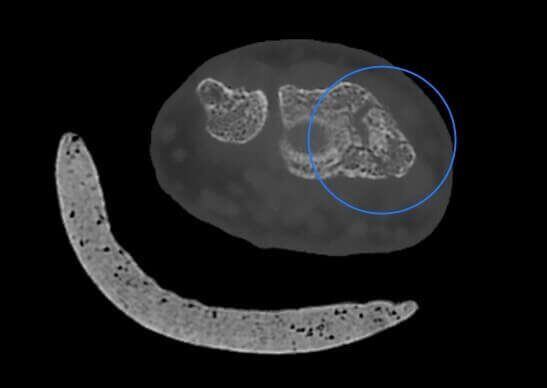

Microfratture di Scafoide